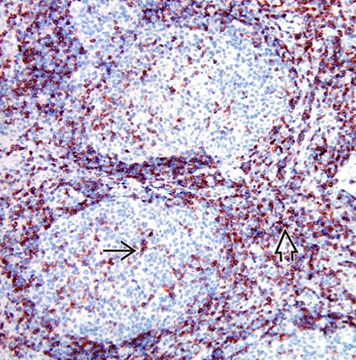

CD3 in reactive follicles. Immunohistochemical stain for the pan T-cell marker CD3 highlights scattered small lymphocytes within germinal centers (solid black line). Many more CD3(+) lymphocytes are noted in the interfollicular region .(open black line) [2]

Immunohistochemical stain for Bcl-6 highlights centrocytes and centroblasts in the reactive germinal centers (open blue arrow) Mantle zone lymphocytes (straight black arrow) are negative; rare or scattered interfollicular lymphocytes (curved black arrow) are positive for Bcl-6. - Ki67 looks similar